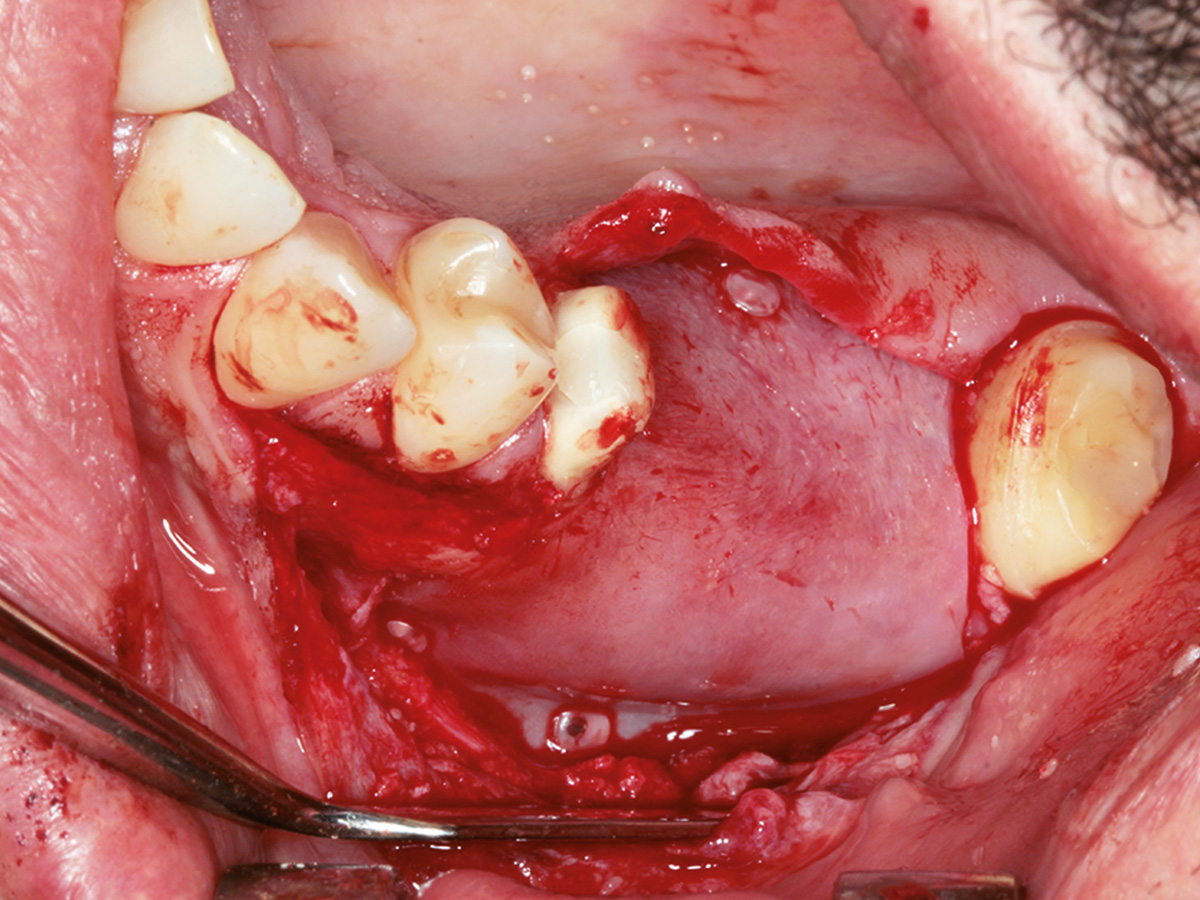

Osseodensifikation ist eine einfach zu erlernende Technik, die hilft, das Implantatlager zu verbessern. Besonders im Oberkiefer, wo weicher Knochen häufig keine ausreichende Primärstabilität bietet, können mithilfe der Densah-Bohrer Verbesserungen erzielt werden, um eine reizfreie Einheilung der Implantate zu gewährleisten. Die aber wohl bemerkenswerteste Eigenschaft der Spezialbohrer ist, dass sich damit absolut minimalinvasive geschlossene Sinusaugmentationen durchführen lassen, was für Patienten sehr angenehm ist. Trotz technischer Innovationen muss in vielen Fällen zusätzlich augmentiert werden. Auch hier kommt den Materialien eine ganz besondere Bedeutung zu. Wird partikulär mit Knochenersatzmaterial augmentiert, müssen Membranen verwendet werden. Unzählige auf dem Markt befindliche Produkte haben sehr unterschiedliche Indikationsbereiche und variieren stark in Ergebnis und Handling.

In diesem Kurs wird das Handling mit der Bone Lamina samt Augmentation geübt. Danach sollte jeder Teilnehmer in der Lage sein, im Praxisalltag Knochen aufzubauen. Dazu ist eine korrekte Schnittführung notwendig, die ebenfalls thematisiert wird. Damit ein Knochenaufbau erfolgreich einheilt, ist der spannungsfreie Wundverschluss zwingend erforderlich. Deshalb wird im Kurs auch besonderes Augenmerk auf spezielle Nahttechniken gelegt, die am Modell und am Schweinekiefer geübt werden.